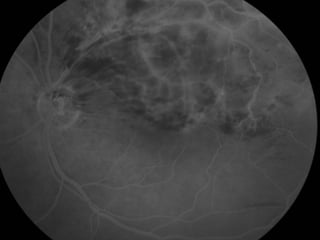

Angiografia 10/02/2009

Caso Clínico

• ANGIOGRAFICO

– Define edema macular, a perfusão da rede capilar para-foveal e a presença de

neovasos.

– Mostra o retardo artério-venoso na arcada comprometida e a presença de

áreas isquêmicas e de vazamento tardio.

Caso Clínico Exame Oftalmológico: AcuidadeVisual c/c: • OD = 20/20 • OE = 20/100 (metamorfopsias) • Add: +3,00 Biomicroscopia: Normal FO: OD: Normal. OE: Hemorragias retinianas temporal superior. Edema Macular Solicitado: Angiografia e OCT